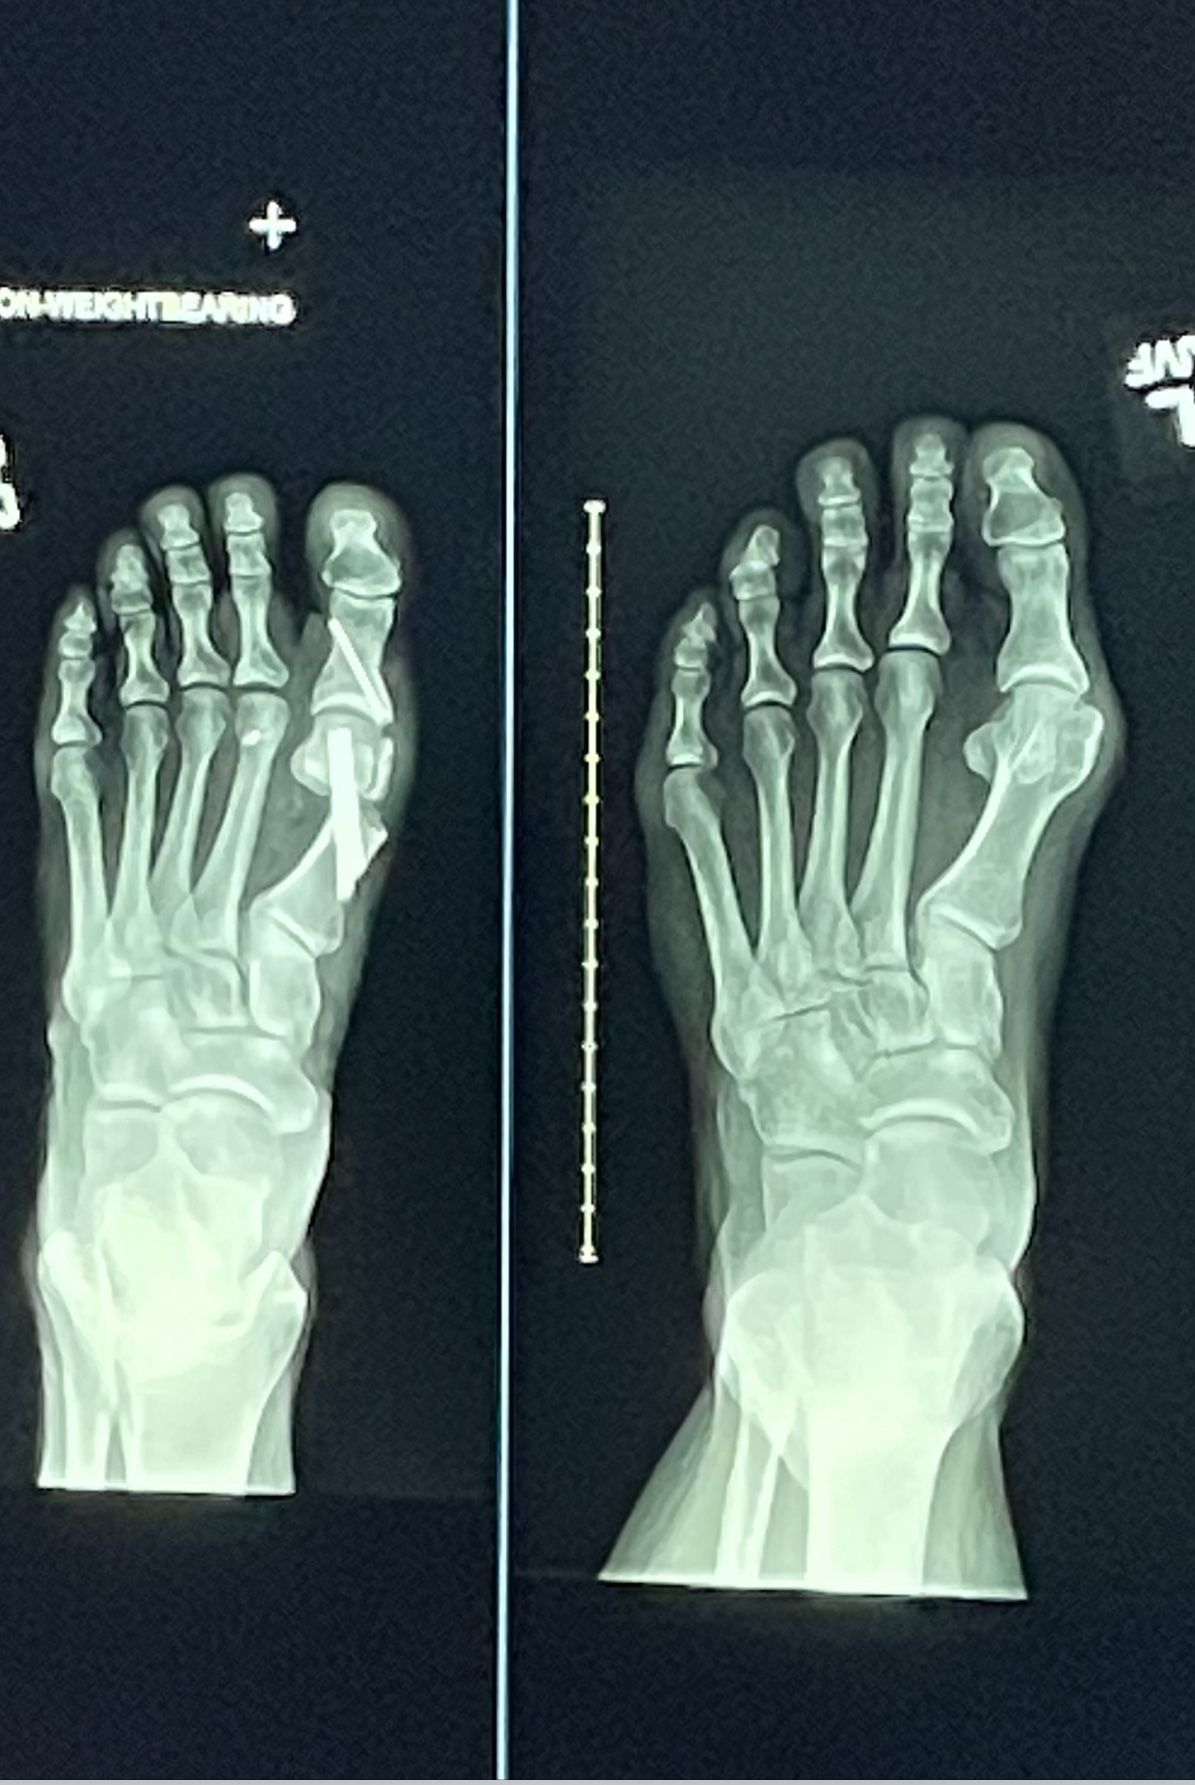

Bild på fötter idag. Högerfotens stortåled sned men inte så värst svullen eller röd/varm. Vänster fot har jag nästan aldrig några problem med men stortån har en liten snedställning (enligt röntgenbilder från när jag var i 20-årsåldern).